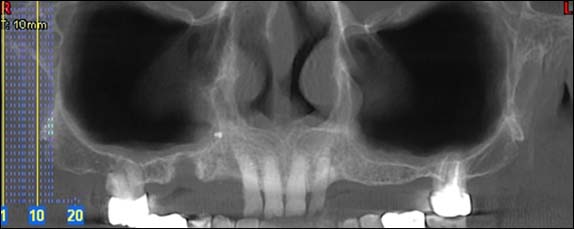

Dernière technologie à notre disposition, cette technique permet de voir en 3 dimensions des images de votre bouche et de mettre en évidence des pathologies ou des anomalies que les autres techniques ne permettent pas d'objectiver.

Reconstruction panoramique

Reconstruction coronale